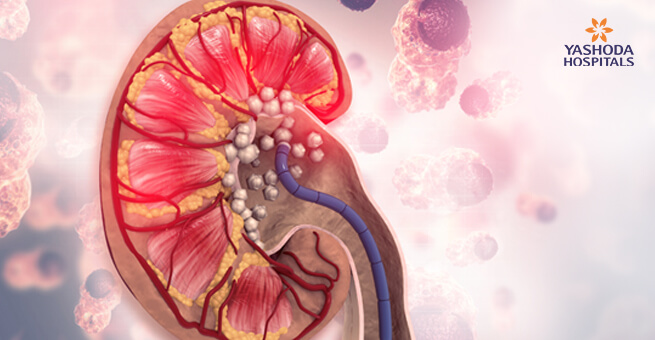

కిడ్నీలో స్టోన్స్ రావడానికి కారణాలు, లక్షణాలు, అపోహలు & వాస్తవాలు

ప్రస్తుత ఆధునిక ప్రపంచంలో కిడ్నీలో రాళ్లు అతి సాధారణమైన సమస్యగా మారుతుంది. ప్రపంచ జనాభాలో 10 నుంచి 15 శాతం మంది ఈ సమస్యతో బాధపడితే మన దేశంలో 5 నుంచి 7 మిలియన్ల ప్రజలు కిడ్నీలో రాళ్ల సమస్యతో బాధపడుతున్నారు. మూత్రపిండాల్లో మినరల్స్ స్పటిక రూపంలో ఏర్పడటాన్ని కిడ్నీ స్టోన్స్ అంటారు. మొత్తంగా చెప్పాలంటే ఆరోగ్యం మరియు దాని శ్రేయస్సు అంతా కిడ్నీలపైనే ఆధారపడి ఉంటుంది.

కిడ్నీలో స్టోన్స్ ఏర్పడడానికి గల కారణాలు

కిడ్నీలో రాళ్లు ఏర్పడడానికి ఒక ప్రత్యేక కారణం అంటూ ఏమి లేదు. అనేక కారణాల ఫలితంగా శరీరంలో అవి అభివృద్ధి చెందుతాయి.